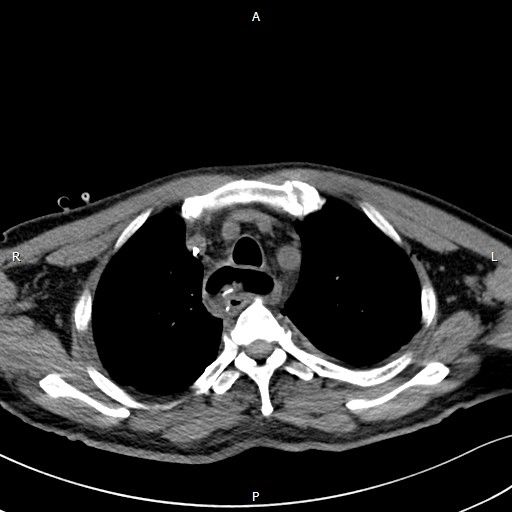

术后胸腔胃

11月6日,手术在全麻状态下进行。患者采取侧卧位,从左侧腋下开口约10厘米。李简教授在助手协同下,成功切除食管肿物,提拉胃部,将食管上部与胃进行充分吻合,并将肿瘤及周围淋巴结一一清除,有效降低食管癌术后并发症。手术涉及腹、胸、颈3个部位,历时5个小时,出血量100ml。术后3天患者已能下床活动,目前,孙叔叔恢复情况良好,可进流食。